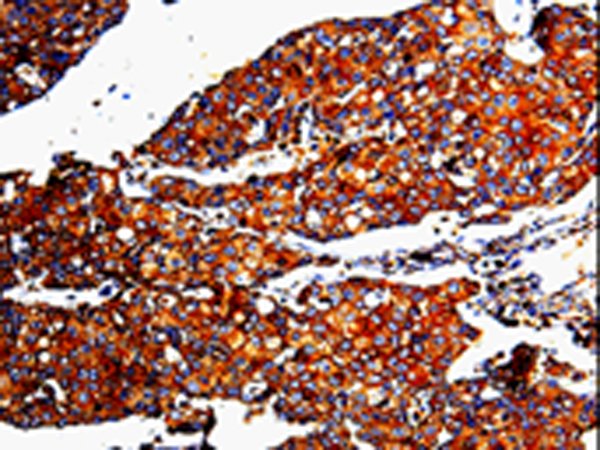

IHC positive control: |

Human breast cancer and Human cervical cancer |

IHC Recommend dilution: |

25-100 |